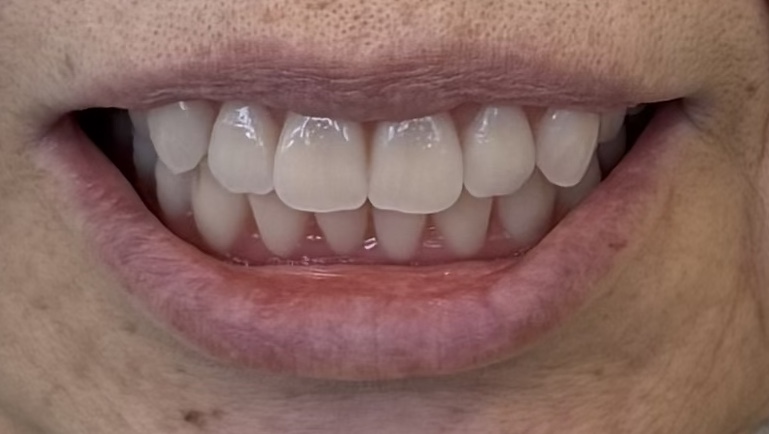

治療後

治療後の口元

インプラントなしでも、ここまで動かない総義歯

- 真っ直ぐ噛んでも、横に歯を擦るように動かしても安定していることが左の動画で確認することができます

最終的には、入れ歯の安定性が向上し、食事の際のズレや不安も軽減され、日常生活における「噛める」という機能を取り戻すことができました。